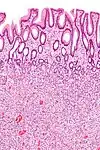

| Adénome dentelé traditionnel | Cryptes dentelées, souvent une structure villeuse, avec atypie cytologique, des cellules éosinophiles | Oui | ![]() |

||